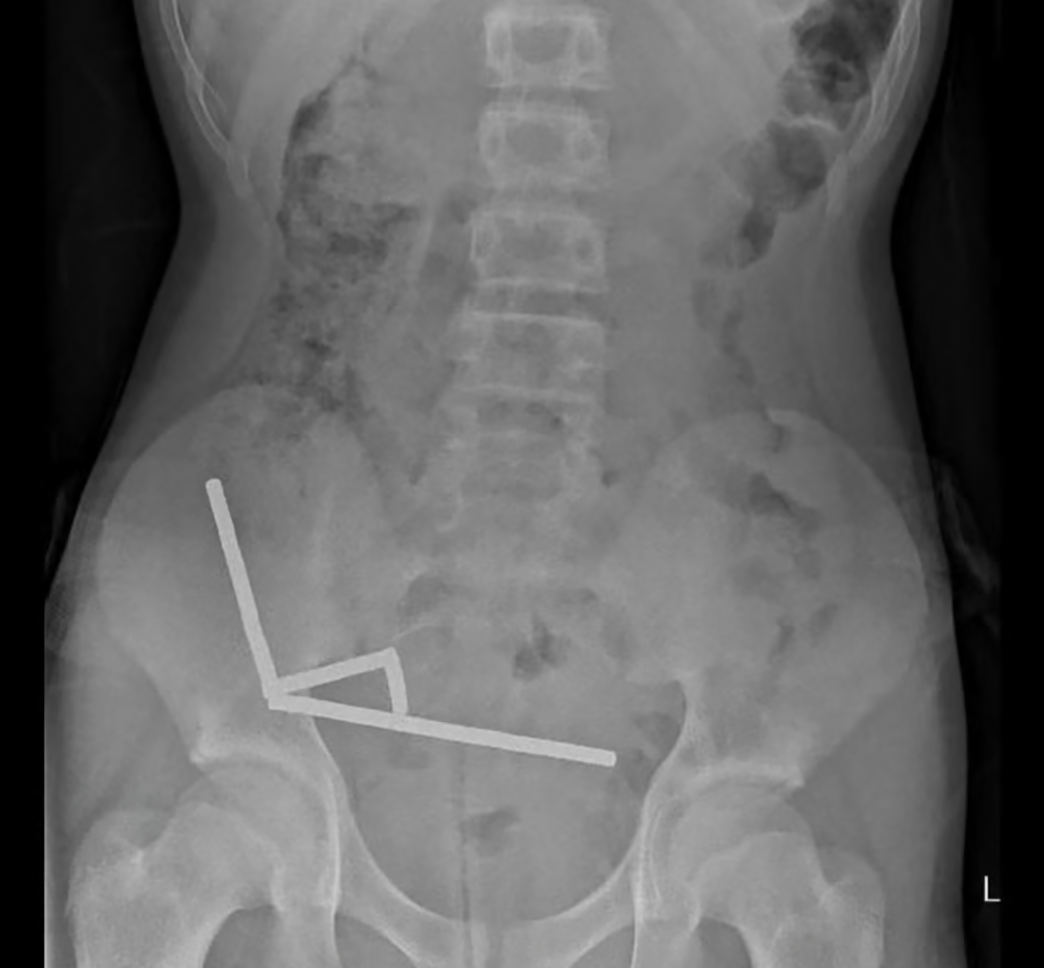

https://www.theguardian.com/world/2025/oct/24/surgeons-remove-high-power-temu-magnets-new-zealand-teenagers-intestines

>Surgeons remove Temu magnets from intestines

One of these fuckers tried to give themselves magic powers by swallowing Chinese magnets.